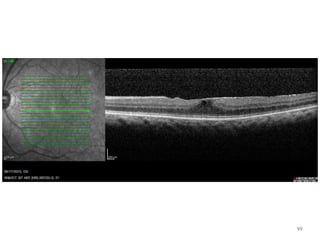

98

99

100